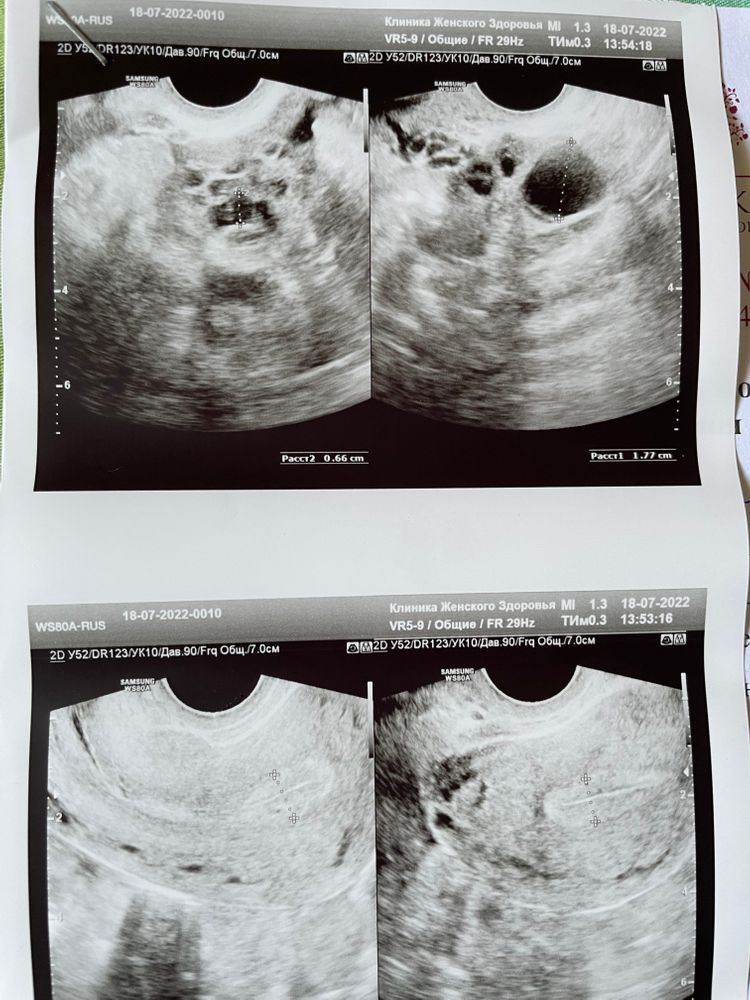

Фолликул или ЖТ?

По всем анализам спкя, сейчас 23 дц и созрел фолликул , сам!!!

сходила на узи. Вчера был 17,7.

Сегодня пришла на фолликулометрию и узистка сказала ,что овуляция видимо была ночью. Есть свободная жидкость. И ЖТ 18.5 .

Но меня терзают сомнения , что это все ещё фолликул.

Посмотрите пожалуйста фоточки 🙏🏻

Да, это фолликул.

От себя скажу, как врач УЗД - я больше не пошла бы к этому врачу, настройки изображения ужасны, а точнее они вообще отсутствуют. Как можно смотреть на такое - хз... От качества изображения, иногда очень многое зависит. Структуры тела матки не видно вообще. Контуры яичника еле видно

Фолликул. За день вырос на 1,5 мм.